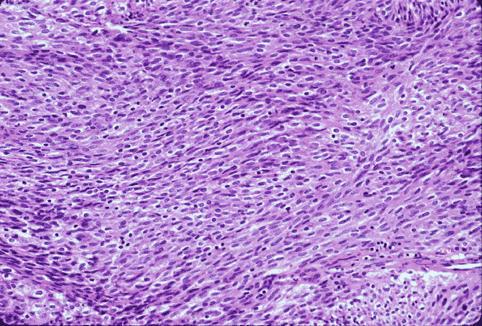

Criteria of Hist.ClassificationMalignant non-epithelilal tumors/Leiomyosarcoma (including GIST)

LocationLarge intestine(Colon)/Rectum

Technique, MethodHistology

Size40 -

Depth of Tumor Invasionsubserosa (subadventitia)